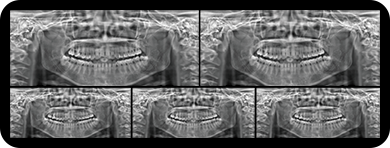

临床样片